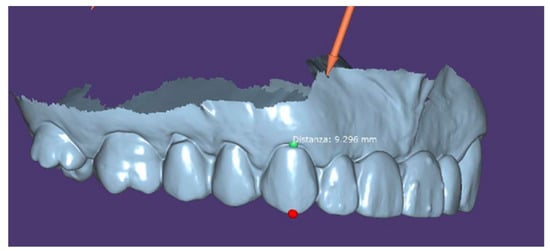

- Instrumental examinations (three-dimensional radiography, intraoral optical impression);

- Image matching and transformation from .dicom to .stl;

- The first design of a prosthodontic with an advantageous position from a biomechanical point of view:

- Implant positioning respecting anatomy as much as possible;

- Realization of definitive prosthetic design;

- Surgical intervention (Figure 5).